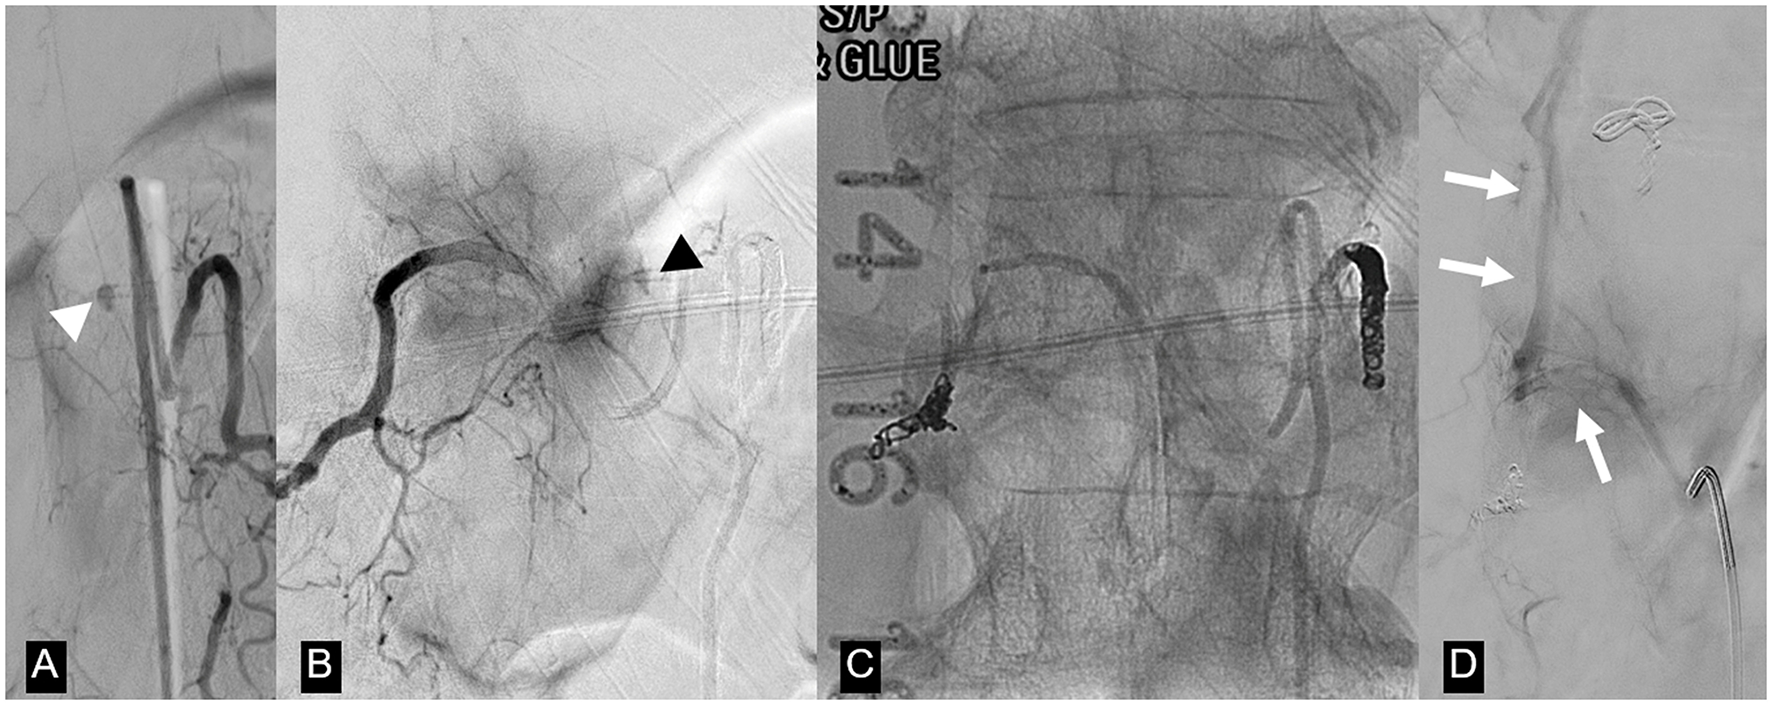

MRI of the spine revealed multicompartmental spinal hemorrhage, in both the subarachnoid and subdural compartments, extending from T7 down to the sacrum, and significant swelling of the lower thoracic cord and the conus medullaris (Figure 2). There was also a trace of intracranial SAH. Contrast-enhanced sequences demonstrated a small, enhanced lesion located posteriorly in the left spinal canal at the T12 level (Figure 2). This was confirmed on spinal angiography to be an ISAA of the left PSAs originating from the left T12 intersegmental artery. The patient was treated by the endovascular coil embolization of bilateral T12 intersegmental arteries to reduce direct and indirect flow to the lesion and to promote thrombosis while sparing the affected PSAs. Postprocedure angiographic acquisitions of adjacent intersegmental arteries did not demonstrate collateral supply to the aneurysm (Figure 3). A follow-up MRI performed 48 h postoperatively no longer showed the focus of enhancement at the T12 level.

A 66-year-old woman on warfarin presented with acute severe low back pain. (A, B, D) T2-weighted MRI images demonstrate conus edema (long arrow) with spinal subdural hematoma, predominantly on the left, displacing the conus to the right (arrowheads). Note the lateral compression of the spinal cord and cerebrospinal fluid by the hematoma (long arrowhead). (C, E) Contrast-enhanced MRI shows focal nodular enhancement at the left peripheral aspect of the cord at the T12 level (short arrow), confirmed later on angiogram as a ruptured left T12 posterior spinal artery dissecting aneurysm (Figure 3A).

Same patient as in Figure 2. (A) Left T12 intersegmental artery (ISA) angiogram demonstrates an oval-shaped dissecting pseudoaneurysm arising from a posterior spinal artery (white arrowhead). (B) Right T12 ISA angiogram postcoil embolization of the left T12 ISA shows retrograde filling of the pseudoaneurysm through retrocorporeal collaterals (black arrowhead). (C) Unsubtracted image of the T12 vertebral body demonstrates coil and n-butyl cyanoacrylate occlusion of bilateral T12 ISAs. (D) Repeat T12 ISA angiogram obtained after the deterioration of the patient 2 weeks after the first embolization shows no filling of the treated aneurysm and a new arteriovenous shunting between the right T12 ISA and the Azygos vein (arrow). This was considered to be incidental and unrelated to the patient's clinical deterioration, but nevertheless embolized via n-butyl cyanoacrylate injection.